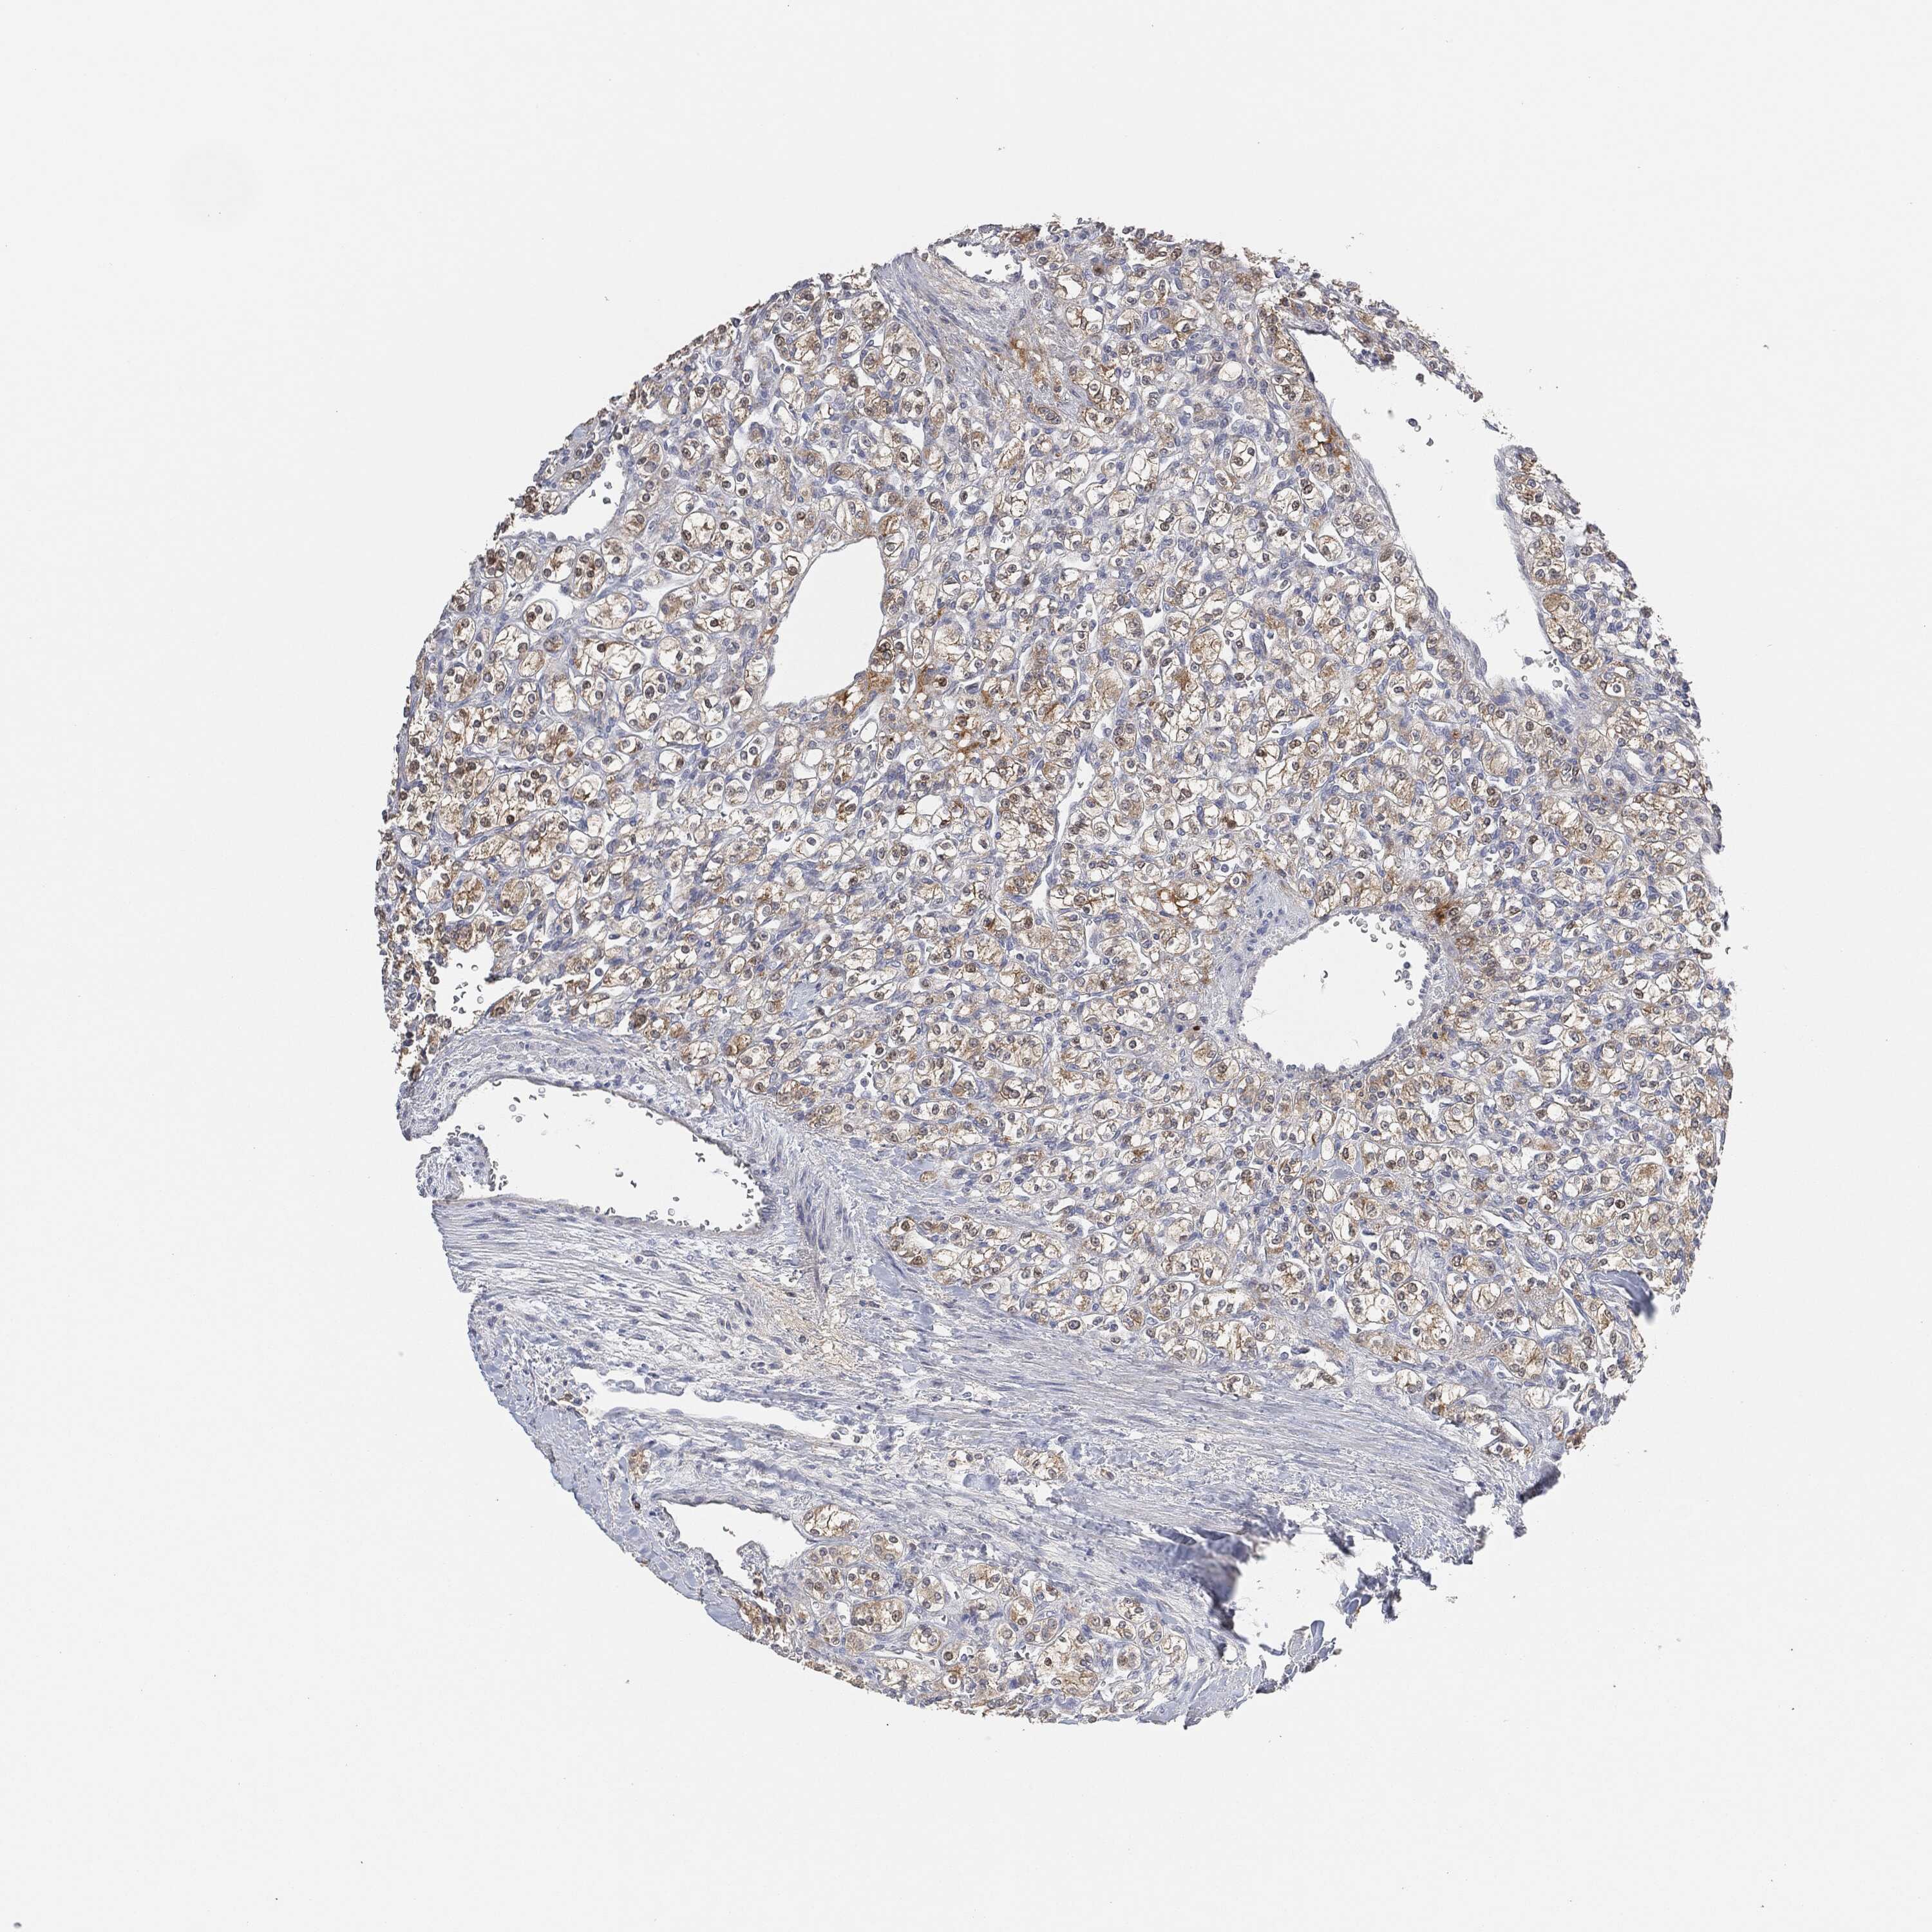

CANCER RENAL CANCER Show tissue menu

KICH TCGA KIRC TCGA KIRC VALIDATION KIRP TCGA PROTEIN RCC CPTAC PROTEIN EXPRESSION